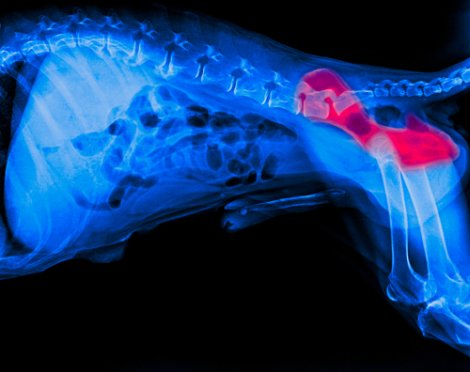

A artrite em cães é uma das doenças crônicas mais comuns, especialmente em cães mais velhos. Em pessoas e cães, essa doença se caracteriza por inflamação, rigidez e dor em uma ou mais articulações.